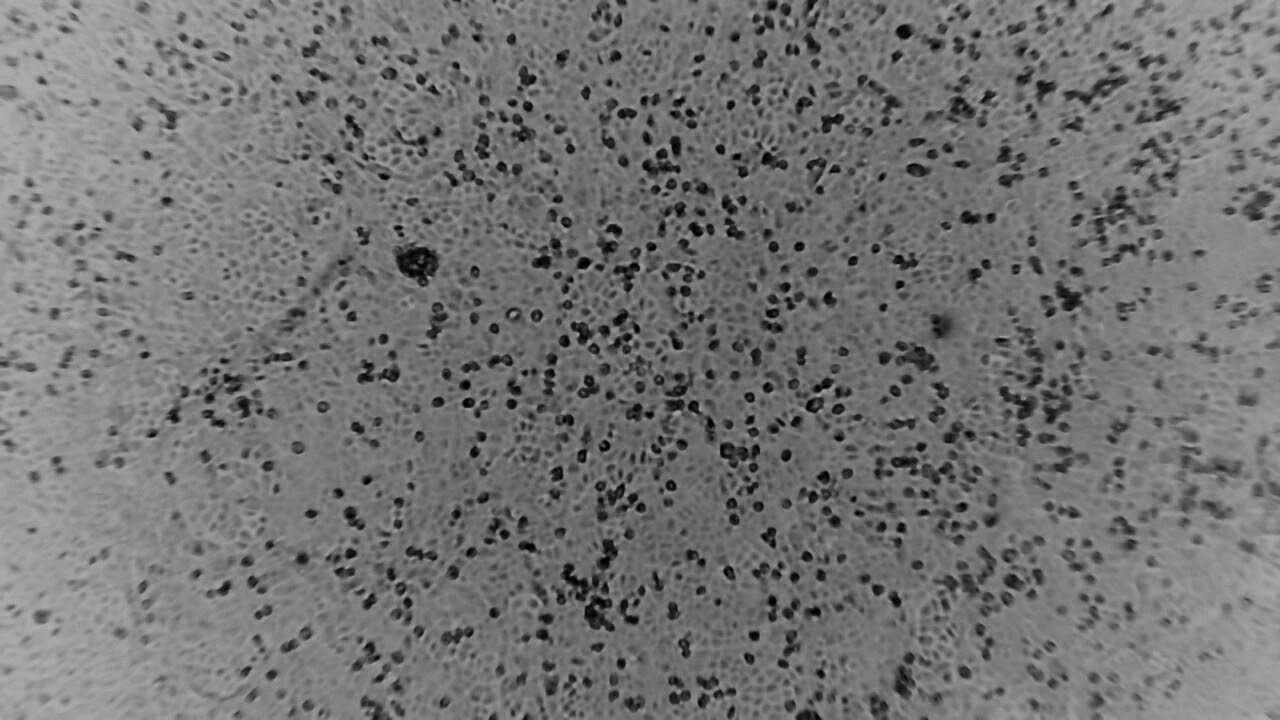

Peter Doherty Institute for Infection and Immunity (Doherty Institute) scientists have successfully grown the 2019 novel coronavirus (COVID-19) from a patient sample, providing laboratories around the world with crucial information to help combat the virus.